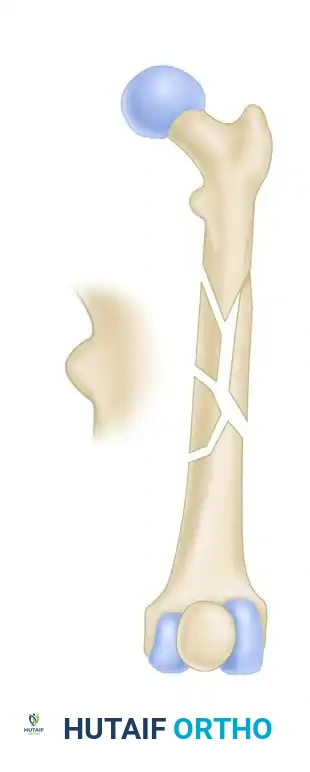

The subtrochanteric region of the femur is defined as the area extending from the lesser trochanter to approximately 5 cm distally into the proximal femoral shaft. This zone is characterized by thick cortical bone and is subjected to massive compressive forces medially and tensile forces laterally.

Fractures in this region are notoriously difficult to reduce and hold due to the powerful deforming forces exerted by the surrounding musculature:

* Proximal Fragment: Flexed by the iliopsoas, abducted by the gluteus medius and minimus, and externally rotated by the short external rotators.

* Distal Fragment: Adducted by the adductor magnus, longus, and brevis, and proximally migrated (shortened) by the hamstrings and quadriceps.